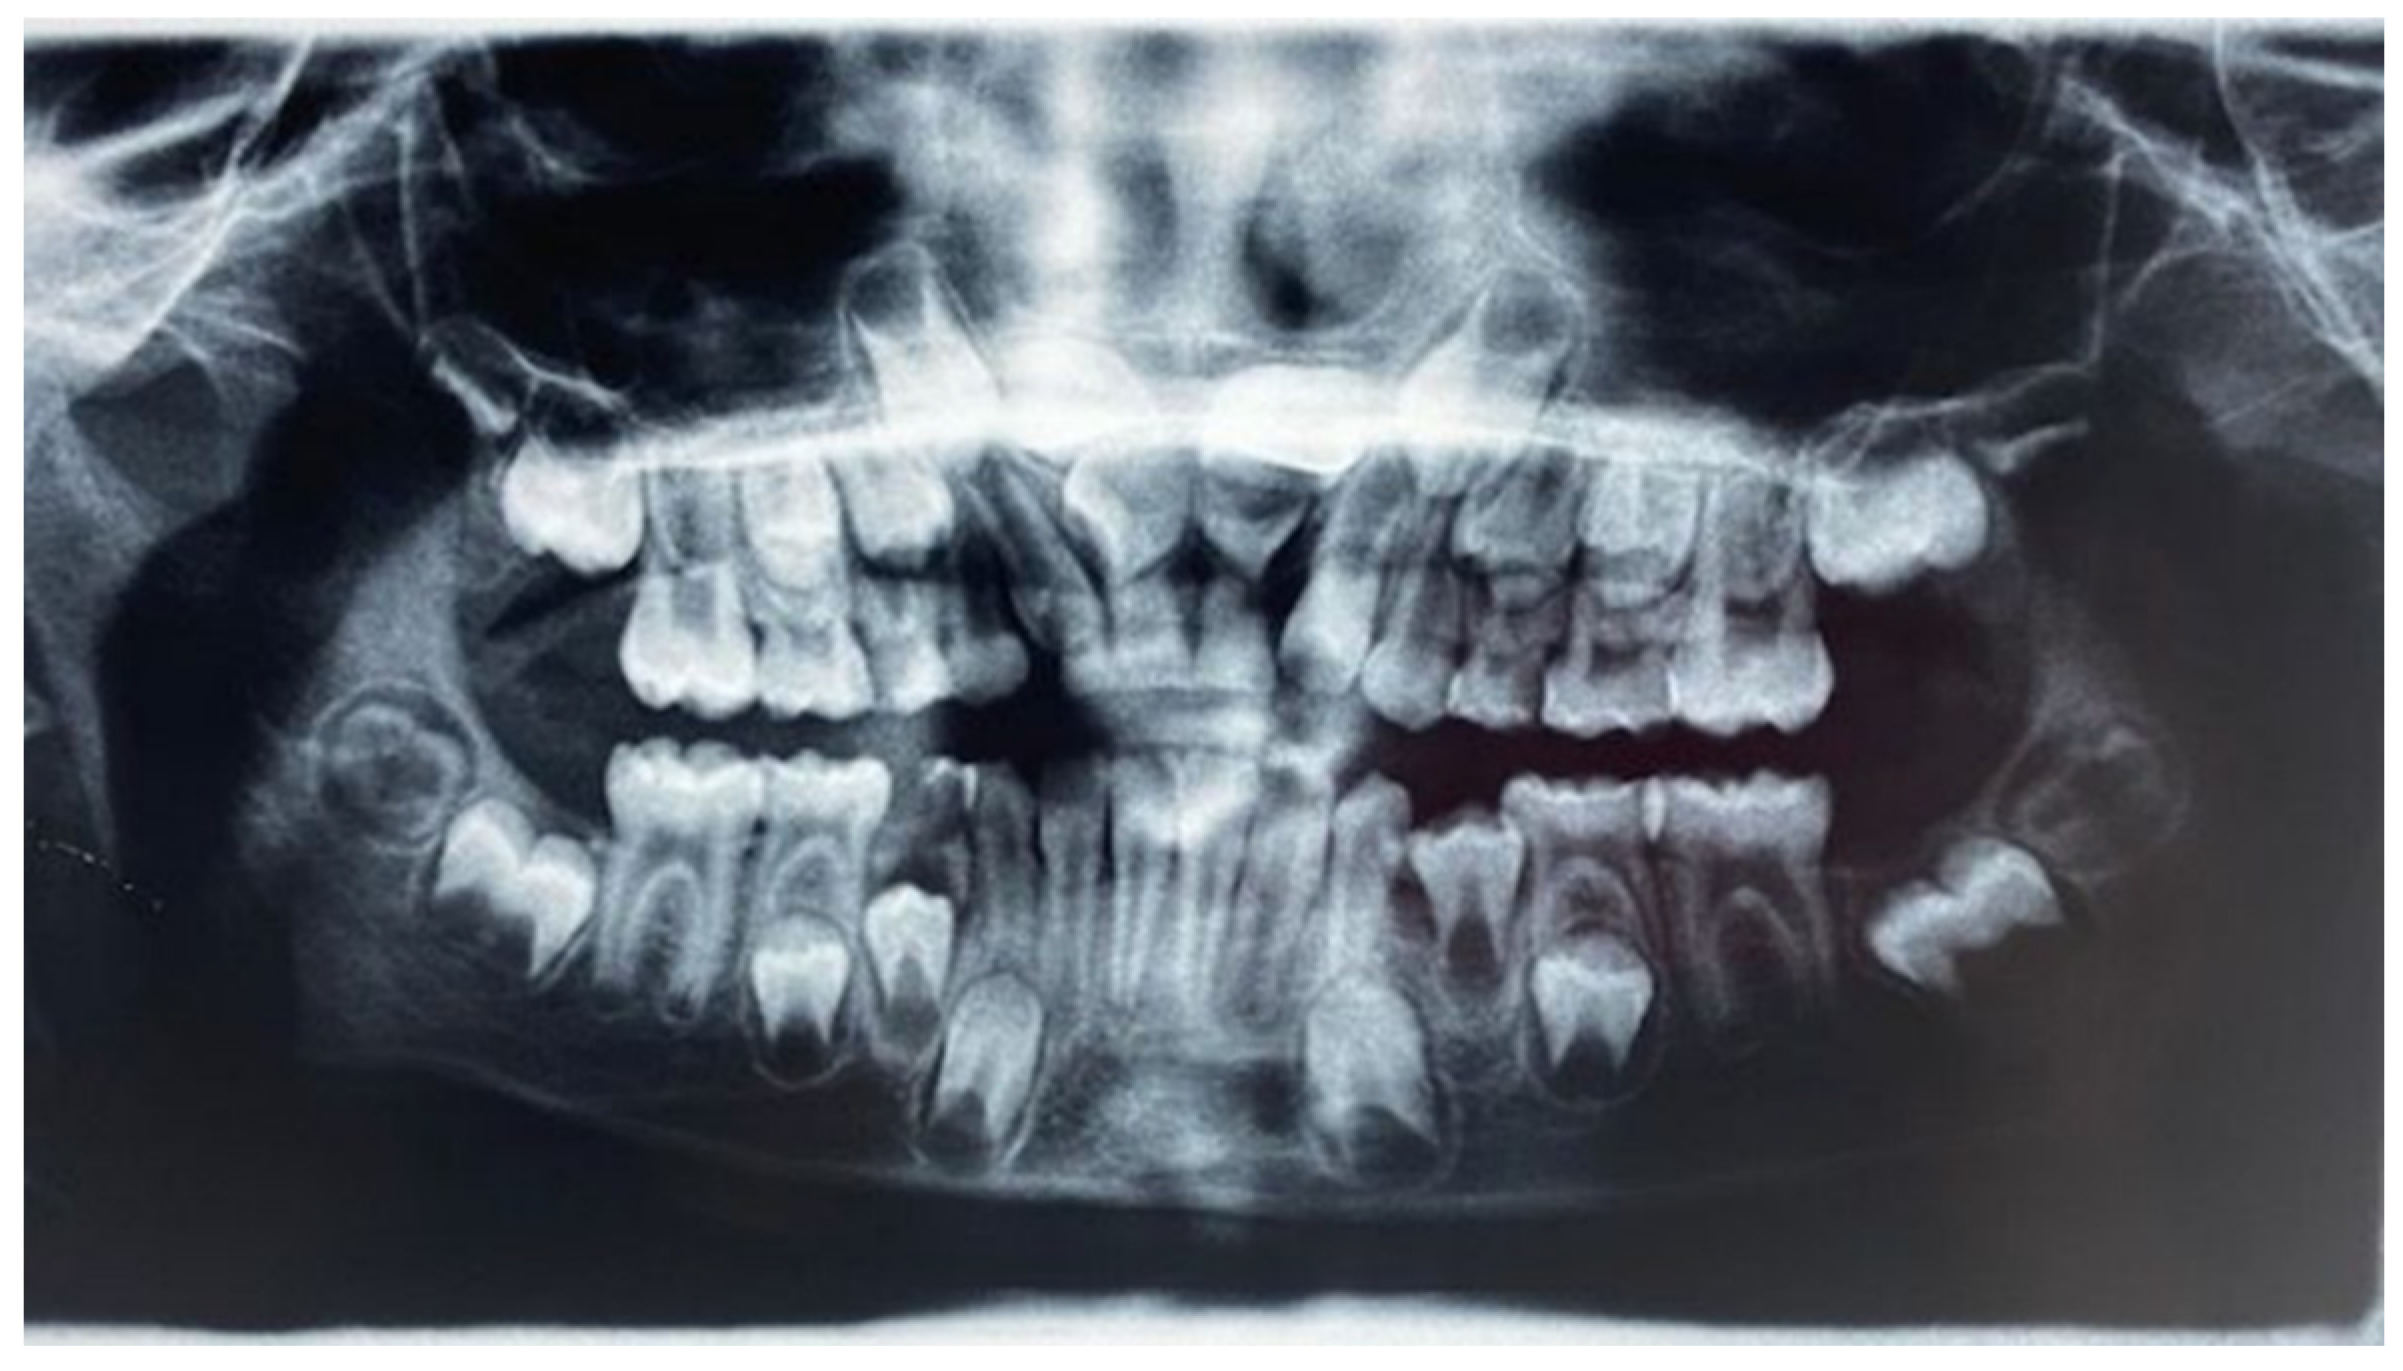

- Ortopanthomography X-ray (OPG X-ray) to evaluate the problem in relation to the entire arch, adjacent tooth and the staging of the eruption of the other dental elements.

- Latero-Lateral Teleradiography (LLT) of the head with cephalometric trace to assess the height and inclination of the crown and root of the impacted tooth.

2.2. Clinical Exams and Diagnosis